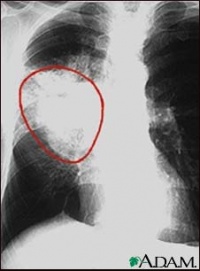

非小细胞型肺癌,包括鳞癌腺癌大细胞癌,与小细胞癌相比其癌细胞生长分裂较慢,扩散转移相对较晚。非小细胞肺癌